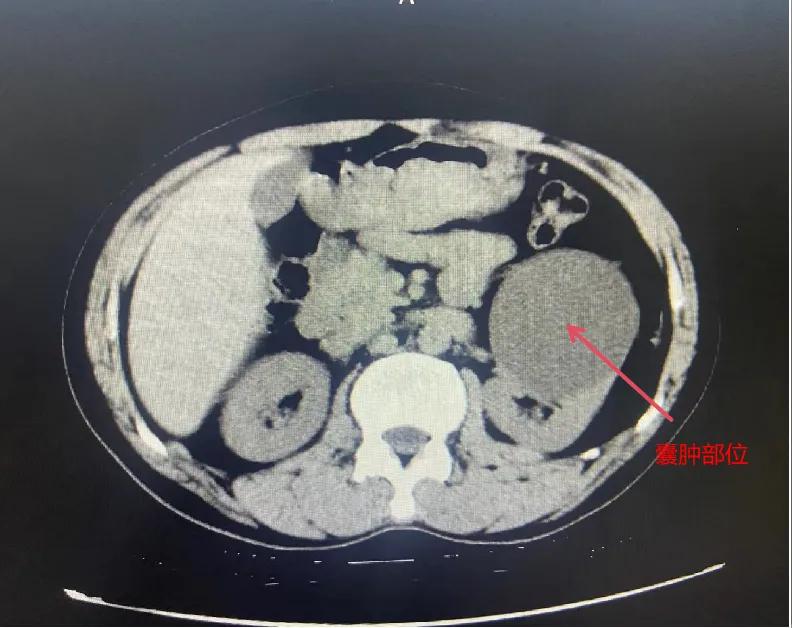

漯河市骨科醫(yī)院泌尿外科開展后腹腔鏡下腎囊腫去頂減壓術(shù)

近日,漯河市骨科醫(yī)院(漯河醫(yī)專二附院、漯河市立醫(yī)院)連續(xù)收治2例腎囊腫患者。泌尿外科主任閆衛(wèi)甫和副主任醫(yī)師王金柱等醫(yī)師團(tuán)隊(duì)經(jīng)討論研究后,決定為患者采取后腹腔鏡下腎囊腫去頂減壓術(shù),經(jīng)過手術(shù)室、麻醉科等科室大力配合成功完成手術(shù)。

閆衛(wèi)甫表示,后腹腔鏡技術(shù)是一種微創(chuàng)外科手術(shù)方法,它通過在后腹腔(即腹膜后的空間)建立一個(gè)手術(shù)空間,利用腹腔鏡器械進(jìn)行手術(shù)操作。這種技術(shù)特別適用于泌尿系統(tǒng)等后腹腔臟器的手術(shù)。與傳統(tǒng)手術(shù)相比具有創(chuàng)傷小、恢復(fù)快、并發(fā)癥少、視野清晰等優(yōu)點(diǎn)。與前腹腔鏡相比則具有對腹腔臟器干擾較少的優(yōu)點(diǎn)。目前,后腹腔鏡手術(shù)主要用于腎囊腫去頂減壓術(shù)、腎上腺腫瘤切除、早期腎癌根治術(shù)、腎腫瘤剜除術(shù)等。

腎囊腫是一種常見的腎臟良性疾病,其發(fā)病率逐年增加。近年來隨著腹腔鏡技術(shù)的迅速發(fā)展,后腹腔鏡下腎囊腫去頂減壓術(shù)成為治療腎囊腫的主要方法。該手術(shù)具有創(chuàng)傷小,手術(shù)時(shí)間短,術(shù)中出血少,術(shù)后康復(fù)快,出院時(shí)間短等優(yōu)點(diǎn),并且術(shù)后復(fù)發(fā)率低,被認(rèn)為是治療腎囊腫的理想術(shù)式。(盧 闖 聶方方 劉 旭 袁錦鈺)